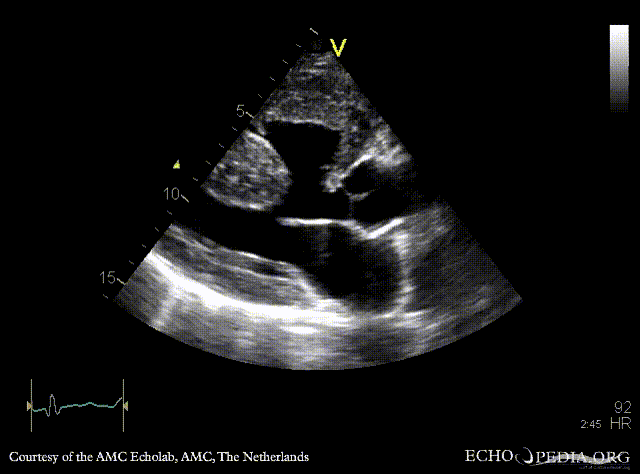

Large VSD, syndrome of Eisenmenger

AMC Echolab, AMC, The Netherlands

A4CH: Color Doppler